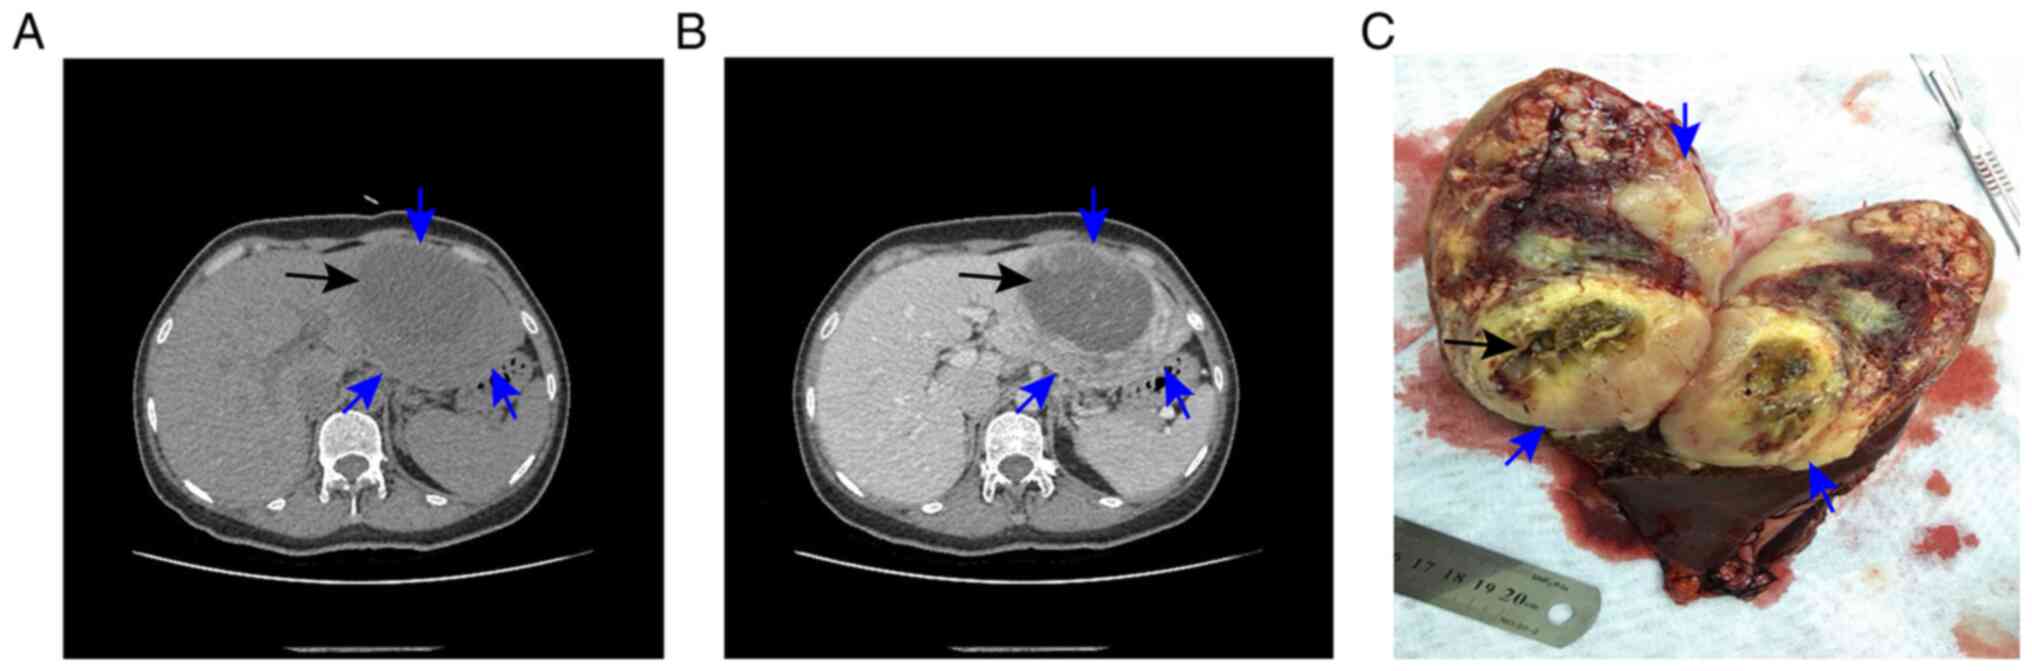

Computed tomography of the abdomen confirmed the presence of the lesion, revealing a low-density mass measuring 11.2×8.5×10.5 cm in the left lobe of the liver, with a lower-density mass measuring 8.5×6.1×5.9 cm in the interior of the tumor (Fig. 1A and B). Based on the analysis of patient history, laboratory data and imaging data, the characteristics of the lesion were different from hepatocelluar carcinoma, cholangiocarcinoma, intrahepatic cholangiocarcinoma, liver abscess and hepatic echinococcosis. Furthermore, IQQA-3D (EDDA Technology, Inc.) imaging of the neoplastic area was performed for precise preoperative evaluation (Fig. 2), and the lesion could be easily removed by radical resection. As suspicion of a malignancy remained high, surgical resection of the left hepatic lobe, including the tumor, was undertaken. Intraoperatively, a tumor (12×10×9 cm), with an unclear boundary, incomplete capsule and fish-like texture, was found in the left lateral lobe of the liver, and a biloma, measuring 8×6 cm, was identified inside the tumor (Fig. 1C). The resection margins were clear.

Figure 1.

IMT upon abdominal computed tomography and its gross morphology. (A and B) IMT on abdominal computed tomography. (C) Gross morphology of the IMT. The blue arrows indicate the IMT and the black arrows indicate the biloma. IMT, inflammatory myofibroblastic tumor.